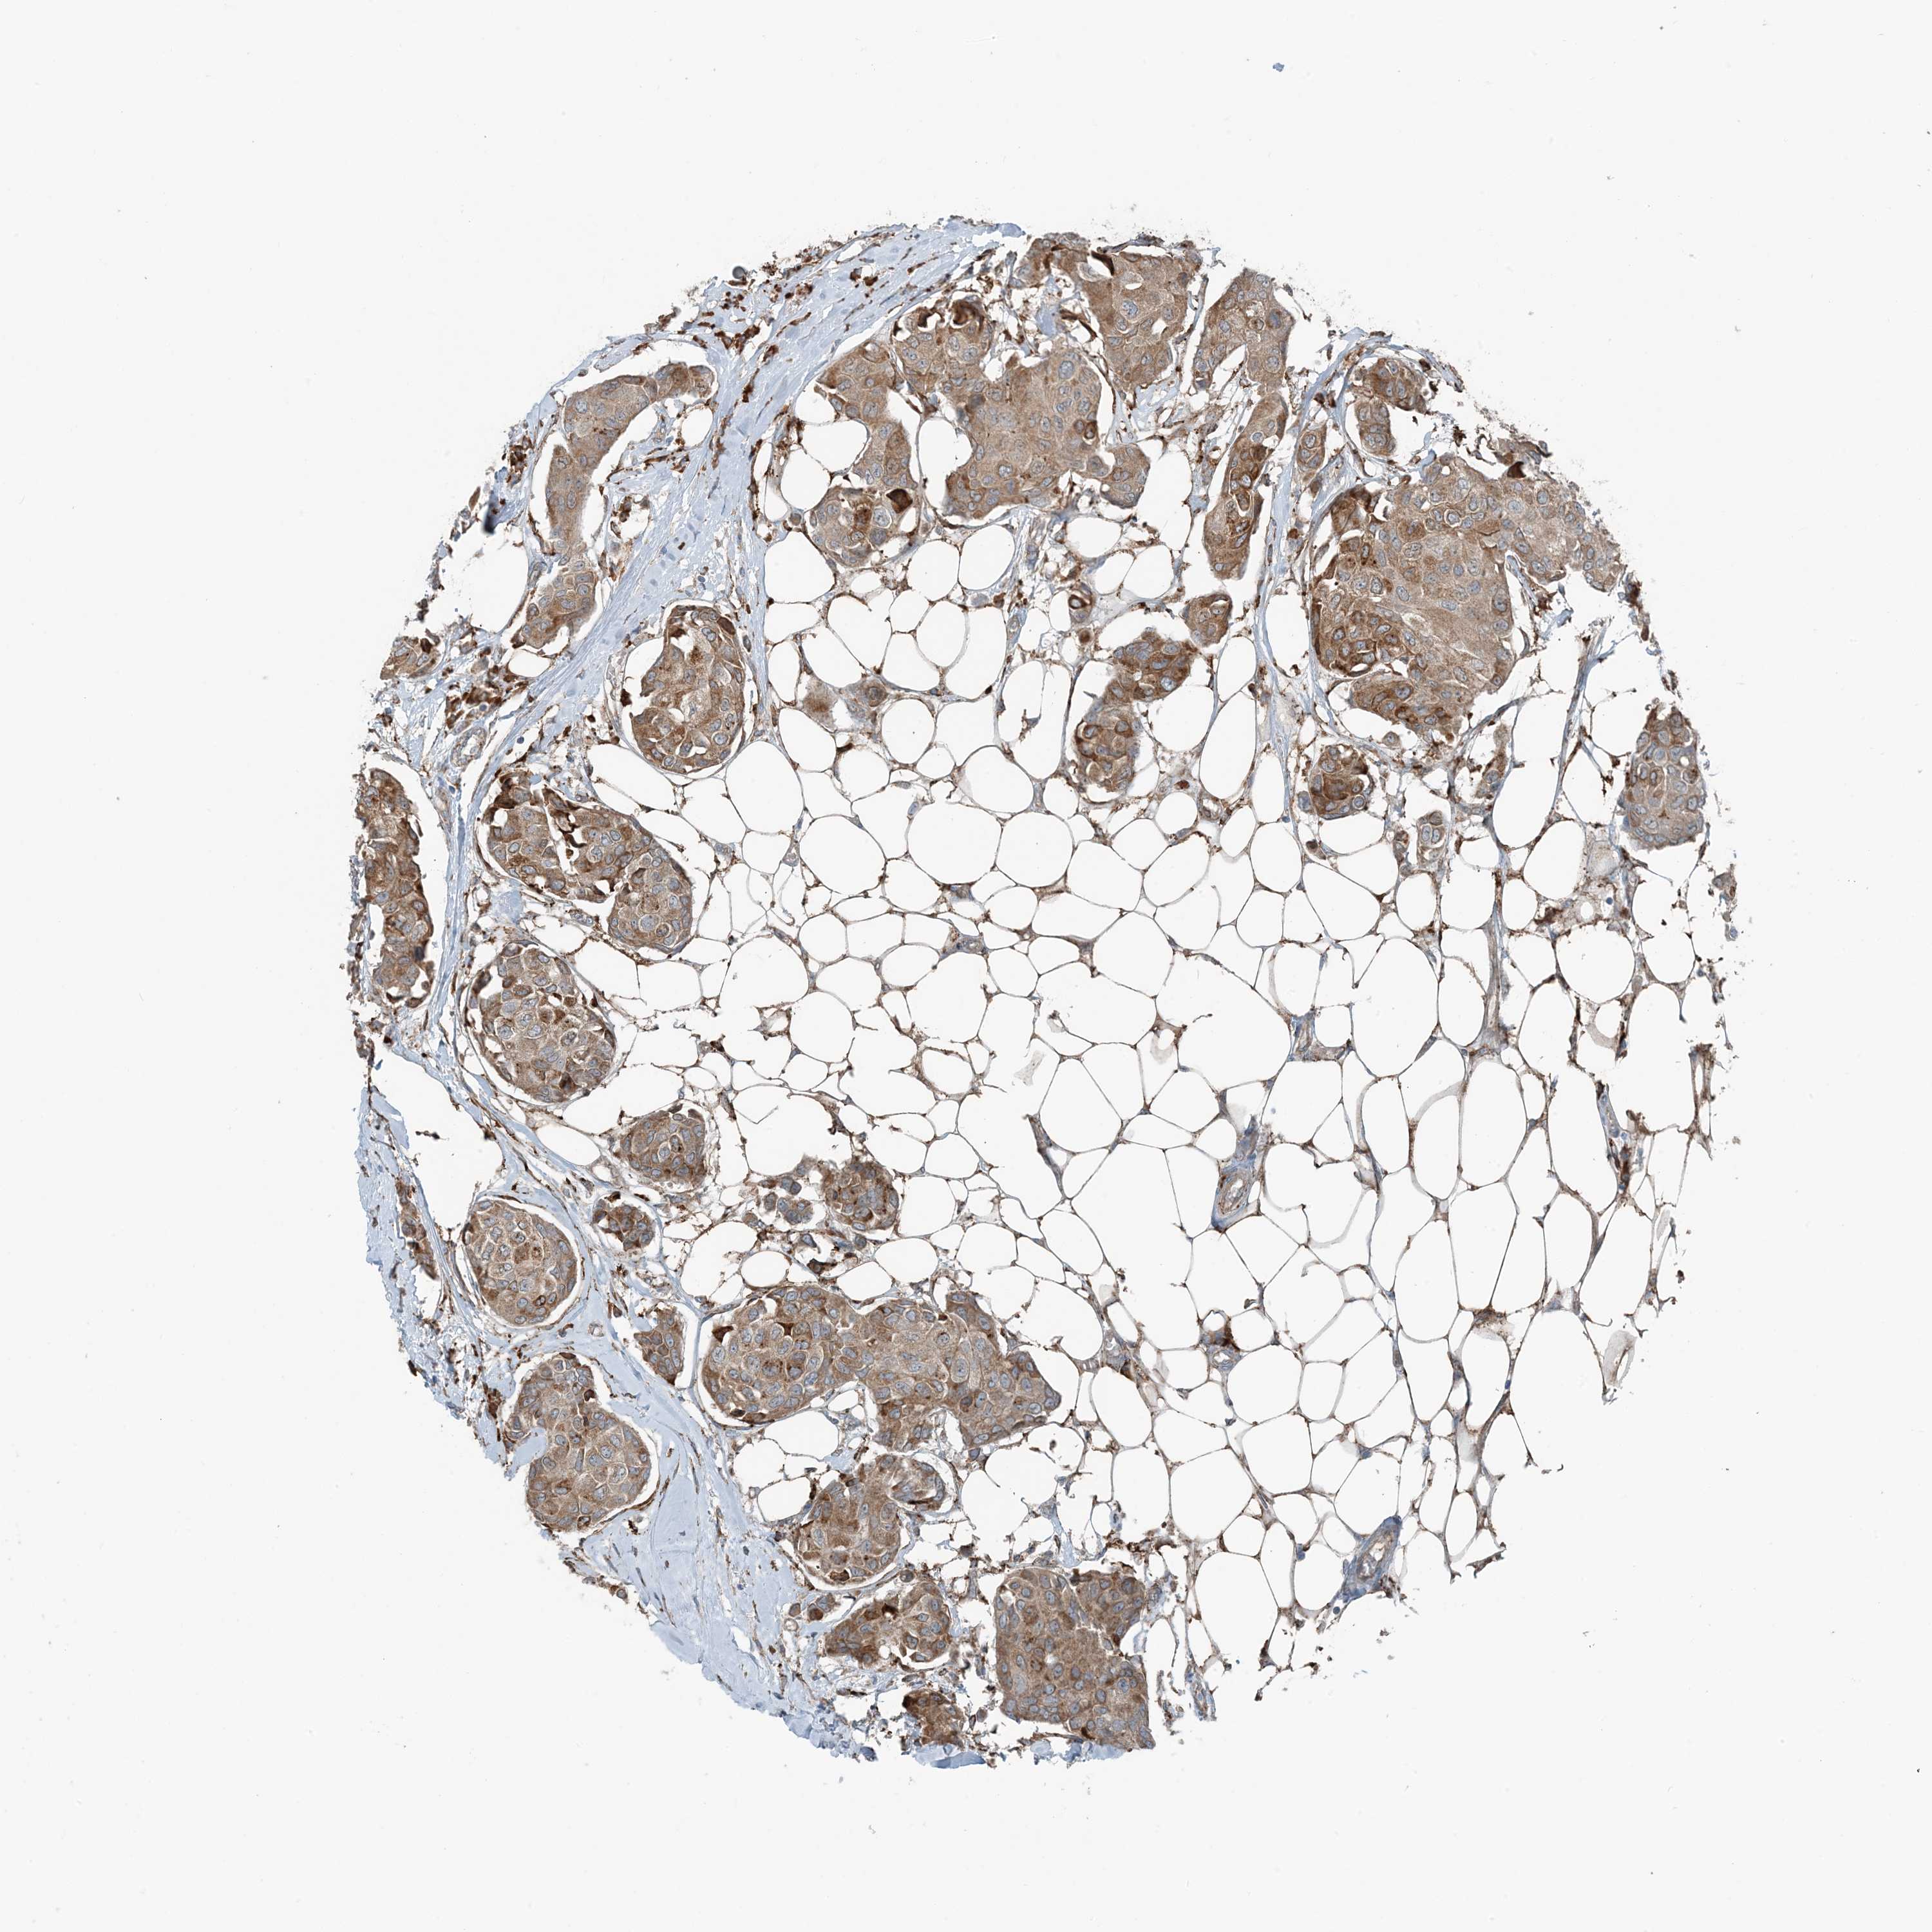

CANCER BREAST CANCER Show tissue menu

BRCA TCGA BRCA VALIDATION PROTEIN EXPRESSION